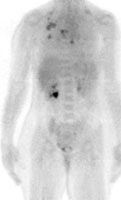

FDG PET exam for the evaluation of locoregional recurrence: The patient shown in the case below had a history of breast cancer and had developed left chest pain. She presented for the evaluation of possible metastatic disease. The CT scan revealed extensive soft tissue thickening in the left breast which was felt possibly related to scar from prior surgery and radiation therapy. There was a 2 cm lymph node in the left axilla (not shown) which was concerning for metastatic disease. Axial (center) and coronal (right) images from the patients FDG PET exam demonstrated marked increased FDG accumulation within the left breast corresponding to the soft tissue abnormality on CT. There were also multiple foci of increased uptake within the the left axilla. Biopsy revealed recurrent breast cancer. Case courtesy of CTI, The power behind PET. |

|